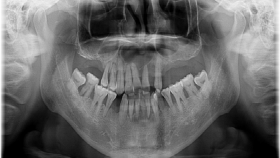

口腔全景片是通过一次X线拍摄,全面反映口腔全貌的检查方式,是一个重要的辅助检查,对牙齿种植、矫正、修复、充填和埋伏牙拔除以及肿瘤的治疗等都有很大帮助。一般来说,口腔全景片可以看到牙齿的解剖结构、牙周状况,是否存在牙槽骨的吸收、有无龋齿的形成,可以定位埋伏牙,观察牙齿与周围的相邻关系。另外,口腔全景片也可以观察上下颌骨、上颌窦、颞下颌关节、髁突的解剖及病理情况,指...

在牙科诊疗过程中,医生通常会先进行数字牙片或口腔全景片的拍摄。那么,为什么在有些情况下还会建议患者接受CBCT(锥形束计算机断层扫描)检查呢?主要原因是,CBCT能够提供更详细的三维图像,帮助医生更清晰地观察牙齿及其周围骨组织的情况。根据放射防护中的ALARA原则(即“尽可能低的合理可实现”的标准),医生会优先选择辐射剂量较低的数字牙片和口腔全景片来进行初步诊断。只有在常规...